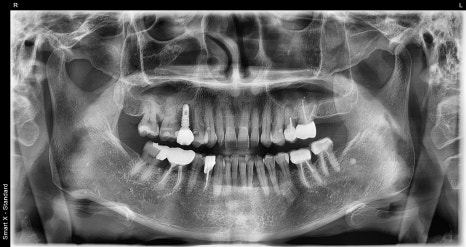

서울오브치과병원에서는 파노라마 촬영과

CT 촬영을 통해 다음을 확인합니다.

잇몸뼈의 두께와 높이

신경의 위치

기존 염증 여부

주변 치아 상태

60대 환자분 역시 이 검사를 통해

“임플란트를 심기 전에 뼈를 보강해야 한다”는

결론을 얻었습니다.

Previous image Next image

이는 환자마다 뼈의 양 · 구조 · 잇몸 상태가

다르기 때문입니다.